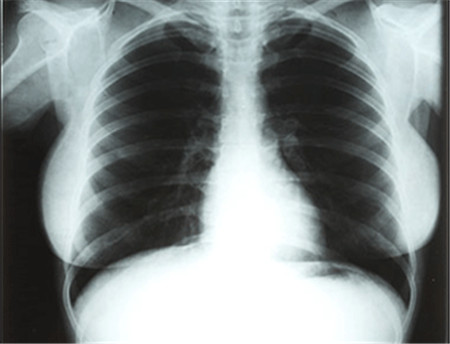

X线检查

子宫虽已超过5个月妊娠大小,但腹部X线摄片见不到胎儿骨骼。X线是一种波长很短穿透能力很强的电磁波。医学上使用的X光检查是指所有使用X光对人体内部进行透视或者摄影的检查方法,其原理是利用X光的穿透作用,由光源的X光管球发出的X光,在穿透人体时,骨、水分(血液等)、软组织(肌肉)等吸收而减弱。